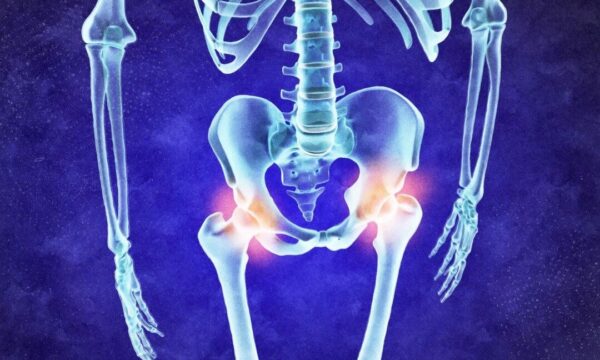

変形性関節症が引き起こすリスクとは? 慢性疾患の連鎖を防ぐ予防法

変形性関節症は治せる? 700の遺伝子が導く未来医療

食事と腸内環境が関節リウマチに影響? 新たな研究結果